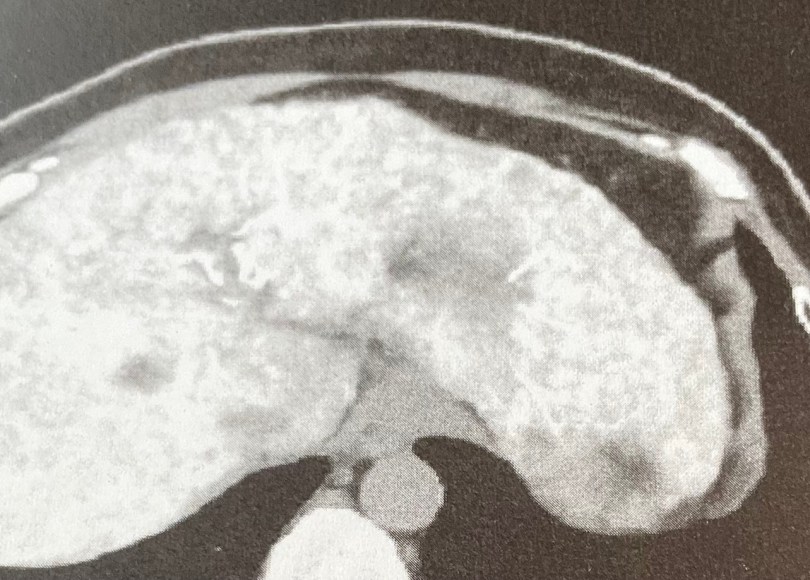

今回の手術は、カテーテルを鼠蹊部から入れて、肝臓内に抗がん剤を満遍なく散布して、腫瘍を消すというもの。

手術を受けた1月14日水曜日の夕方に、主治医さんが病室にいらして、この写真を私に見せて、「ねー綺麗に染め上がってるでしょー」と自慢げにおっしゃいました。

……………染め上がってるってさあ…‥

藍染めか。いや抗がん剤染めだぞ。